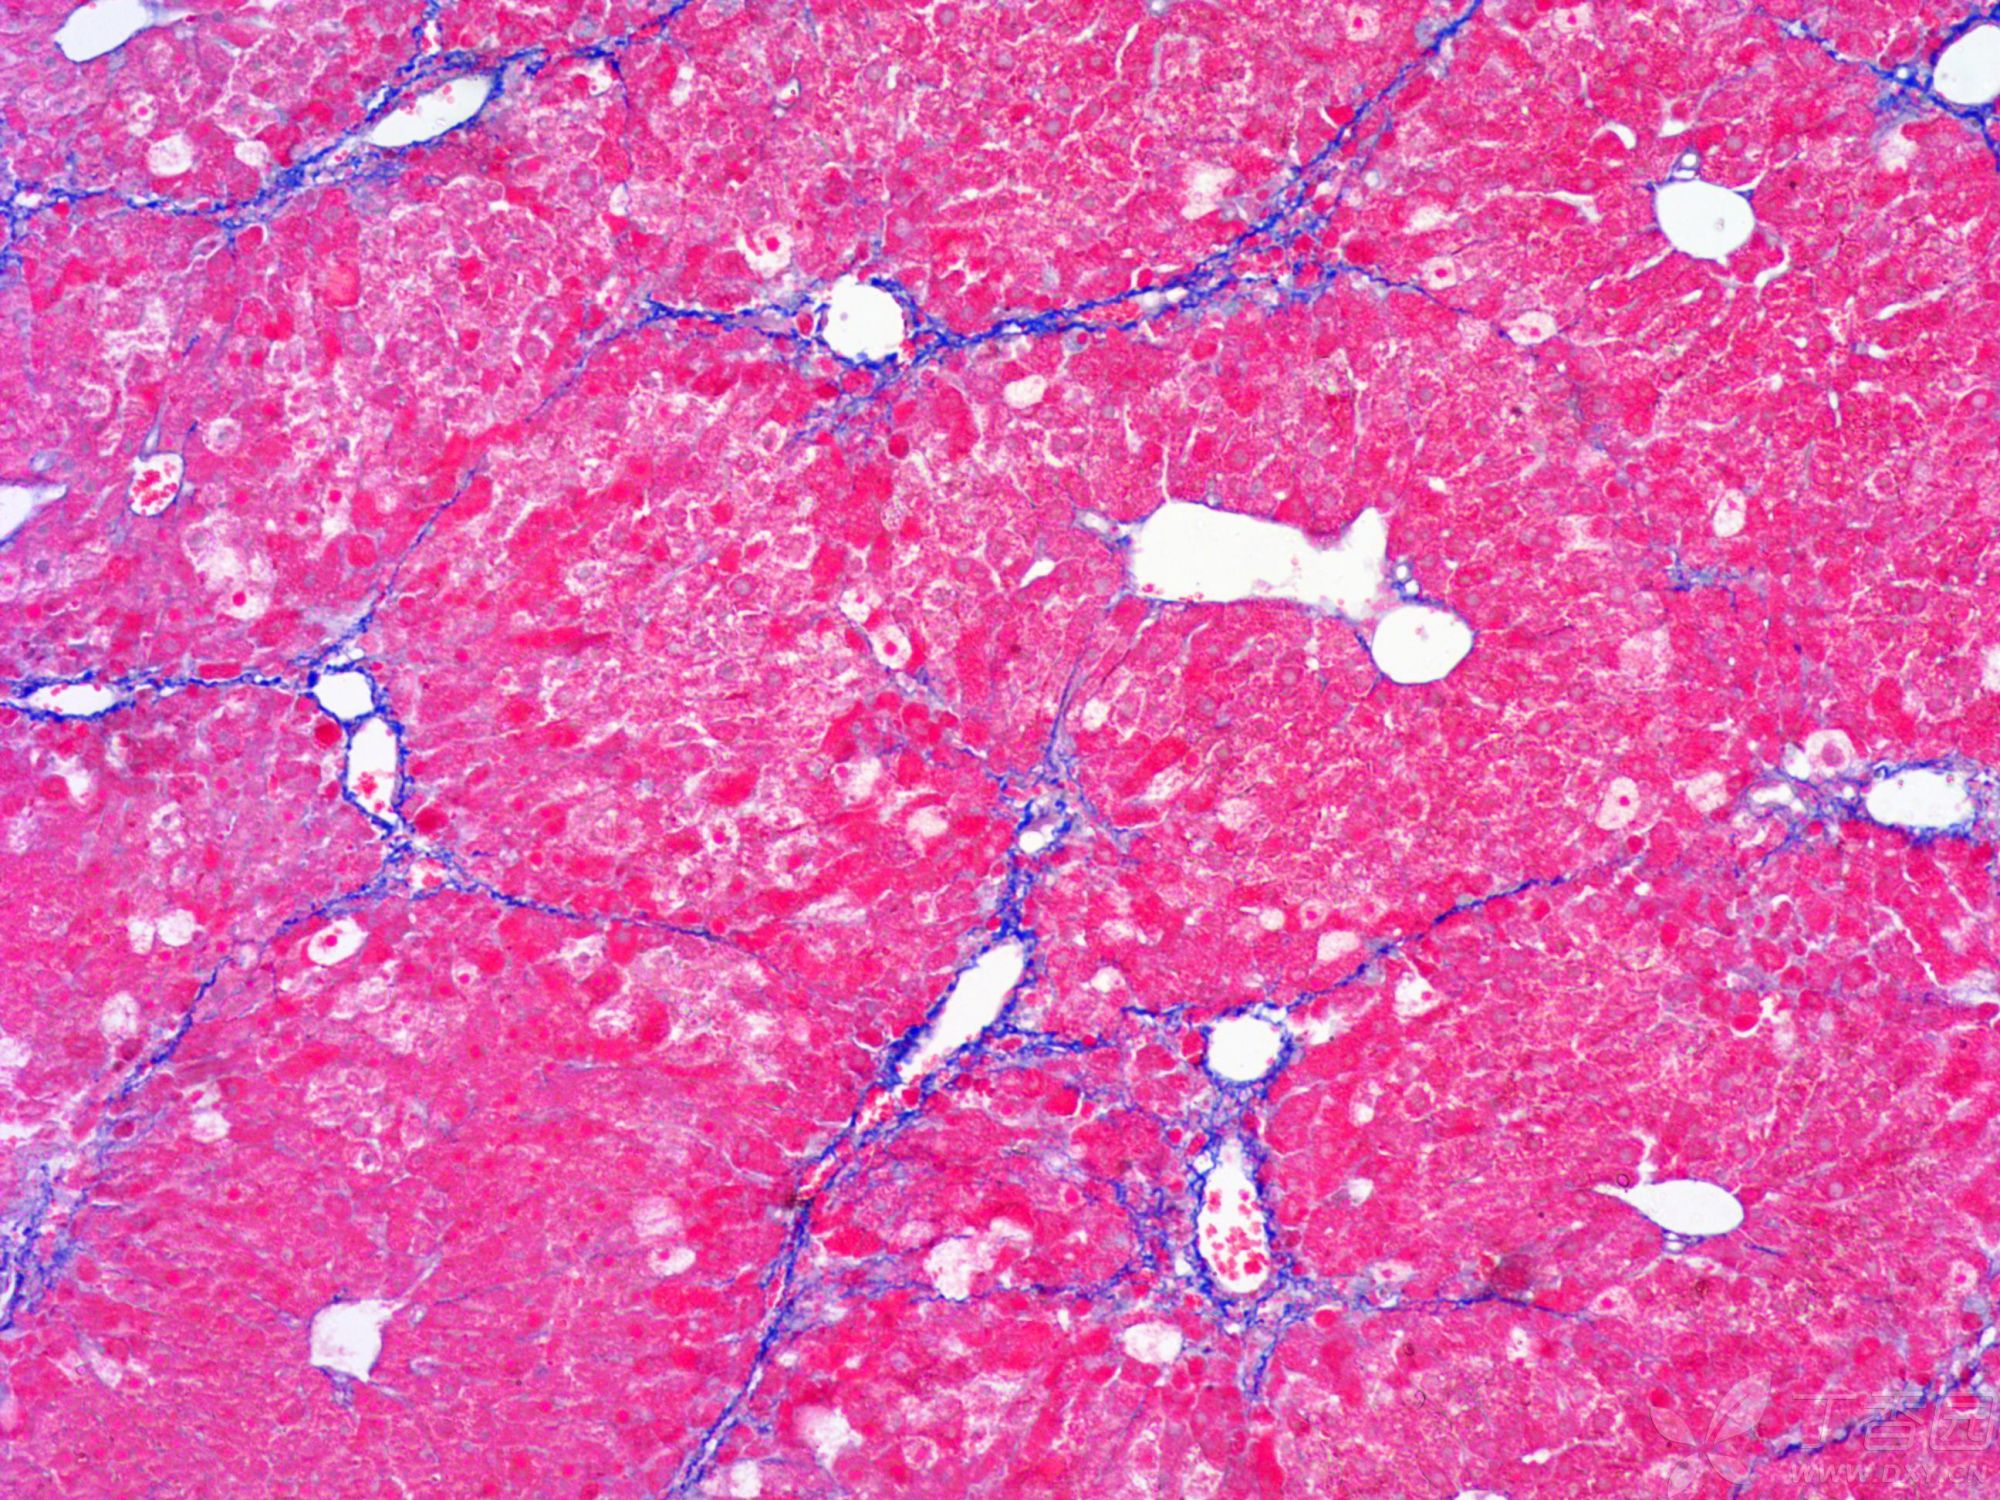

在實驗室中,MASSON染色方法的應用十分廣泛。首先,它可以用于研究組織的纖維化過程。通過觀察膠原纖維的分布和形態變化,研究人員可以了解組織纖維化的程度和進展情況,為疾病的診斷和治療提供重要依據。其次,MASSON染色還可以用于區分不同類型的組織成分,如肌肉、神經膠質等,從而更全面地了解組織的結構和功能。MASSON染色由普拉特澤生物為大家總結分享,普拉特澤生物病理實驗平臺專業承接HE染色外包石蠟切片、冰凍切片等病理實驗代做服務,積累專業豐富的實驗操作經驗。

MASSON染色

●觀察與分析:通過顯微鏡觀察染色后的組織切片,分析膠原纖維、肌纖維等組織結構的分布、形態和排列情況。

小鼠纖維化

在組織學研究中,MASSON染色可以幫助我們觀察和分析不同組織類型的形態和分布。例如,在肌肉組織研究中,MASSON染色可以清晰地顯示肌纖維的走向和排列方式,為我們揭示肌肉組織的生理結構和功能提供有力支持。